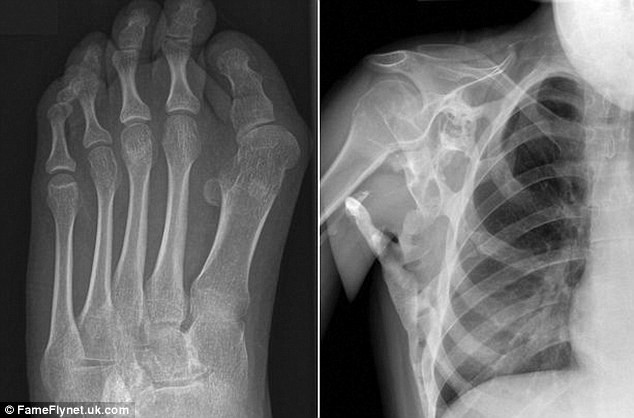

Căn bệnh kỳ lạ này khiến cho toàn bộ cơ bắp và các dây chằng trong cơ thể của Seanie đều bị đông cứng không thể hoạt động các chức năng cử động bình thường.

Hiện tại, cổ tay của Seanie đã bị cứng lại khiến chúng trở nên bất động. Ngoài ra, cơ và xương hai bên bả vai của cô cũng hoàn toàn bị tê liệt.